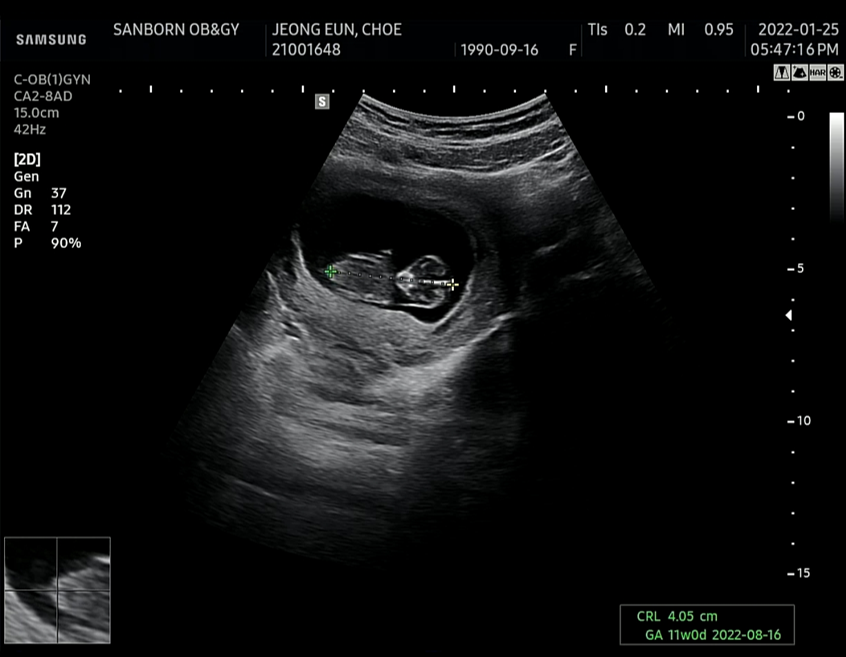

[10주차 호띵이 초음파 (10주차)]

위의 초음파영상을 보면서 호띵이가 8주차 대비 2배나 큰것을 알 수 있었다.

- 7주차 : 1cm 미만

- 8주차 : 1.98cm

- 10주차 : 4.05 cm (8주차 대비 2배나 컸다)

호띵엄마 말로는 의사선생님께서 별 탈 없이 아주 잘자라고 있다고 해서 기다리다가 지쳤던 마음이 금새 풀렸다.

초음파 영상을 쭉 보면 처음에는 아주 얌전히 있던 호띵이가 심장박동수 체크를 하니 팔과 다리를 우렁차게 움직이는 모습을 보면서 호띵이가 심장박동 체크하는 것을 얼마나 힘들어하면 애가 저렇게 움직일까 싶다가도 호띵이 팔 다리 그리고 귀와 머리가 아주 잘 크고 있는 것을 보면서 내심 뿌듯했다. 엄마 뱃속 아주 작은 공간에서 꿋꿋히 잘 버티는 호띵이의 모습이 기특했기 때문이다.